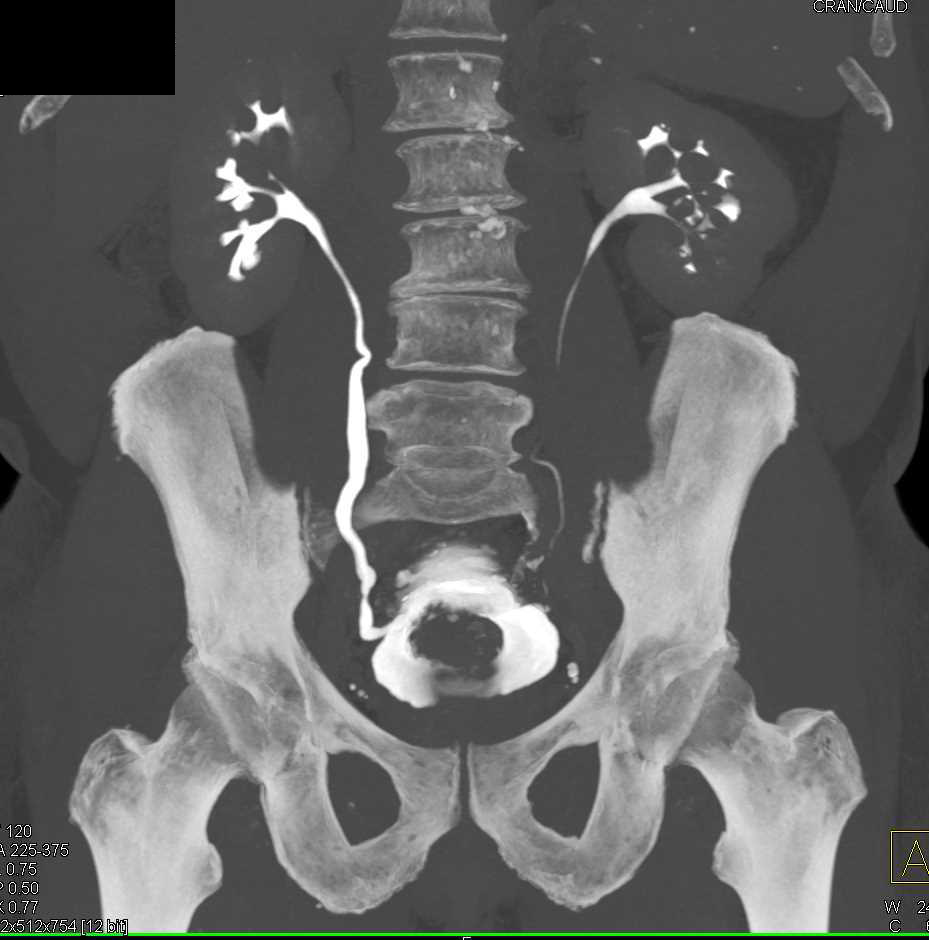

Enlarged Prostate with Bladder Outlet Obstruction Genitourinary Case Anatomical Bladder Outlet Obstruction Fetal bladder outlet obstruction (or lower urinary tract obstruction [luto]) is most commonly caused by posterior urethral valves and urethral atresia and can lead to abnormal renal. Obstructive uropathy is a disorder of the urinary tract that occurs due to obstructed urinary flow and can be either structural or functional. The urethra is the tube that. It reduces or stops. Anatomical Bladder Outlet Obstruction.

Enlarged Prostate with Bladder Outlet Obstruction Genitourinary Case Anatomical Bladder Outlet Obstruction Primary bladder neck obstruction (pbno),. Bladder outlet obstruction (boo) is a blockage at the base of the bladder. This paper outlines the presentation, evaluation, and management of bladder outlet obstruction (boo) in women as it relates to iatrogenic, anatomic, and. Bladder outlet obstruction can arise from a number of conditions affecting the urethra and/or bladder outlet but is most commonly.. Anatomical Bladder Outlet Obstruction.

Enlarged Prostate with Bladder Outlet Obstruction Genitourinary Case Anatomical Bladder Outlet Obstruction Primary bladder neck obstruction (pbno),. The urethra is the tube that. Bladder outlet obstruction can arise from a number of conditions affecting the urethra and/or bladder outlet but is most commonly. It reduces or stops the flow of urine into the urethra. Bladder outlet obstruction (boo) is a blockage at the base of the bladder. Fetal bladder outlet obstruction (or. Anatomical Bladder Outlet Obstruction.

Enlarged Prostate with Bladder Outlet Obstruction Genitourinary Case Anatomical Bladder Outlet Obstruction This paper outlines the presentation, evaluation, and management of bladder outlet obstruction (boo) in women as it relates to iatrogenic, anatomic, and. Primary bladder neck obstruction (pbno),. Obstructive uropathy is a disorder of the urinary tract that occurs due to obstructed urinary flow and can be either structural or functional. Bladder outlet obstruction (boo) is a blockage at the base. Anatomical Bladder Outlet Obstruction.